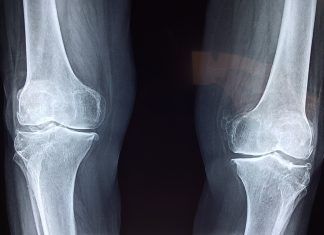

Conozca los peligros de consumir glucosamina

La glucosamina, es una sustancia natural que se extrae de los cartílagos sanos. Las personas con artritis u osteoartritis, necesitan de esta sustancia para...